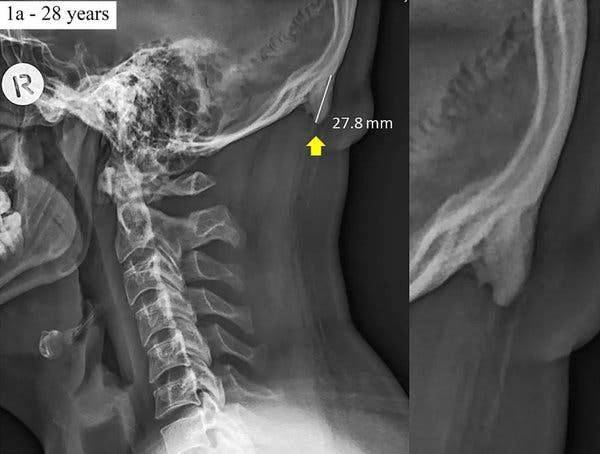

20일 WP 보도에 따르면, 이 논문의 공동저자인 데이비드 샤하르 박사와 마크 세이어스 교수는 3년 전쯤부터 퀸즈랜드 지역에서 촬영된 각 연령대 사람들의 목 엑스레이 사진들을 분석한 결과, 젊은 성인들의 목에서 뿔 모양의 뼈가 있다는 사실을 알게 됐다. 먼저 2016년에 발표한 학술 논문에선 18~30세 성인 218명의 엑스레이 사진들을 표본으로 조사했고, 이들 가운데 41%에서 ‘뿔’이 있는 것으로 나타났다고 밝혔다. 지난해 논문에선 조사 범위를 좀 더 넓혔다. 18~86세 성인 1,200명의 엑스레이 사진을 살펴봤더니 33%에서 문제의 ‘뿔’이 발견됐다. 특히 나이가 많은 성인일수록, 뿔의 길이는 짧은 것으로 파악됐다.